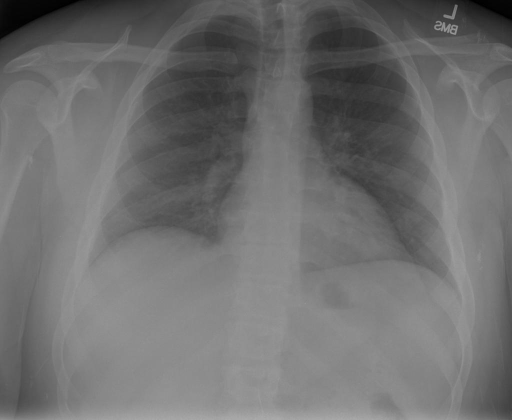

|X光影像|诊疗报告(医生)|XrayGLM|

||心影形态在正常范围内。没有急性骨质异常。有可能出现没有明显的吸水或肺实质状况的线索。没有大面积积液或气胸。有可能怀疑其有误吸或肺实质问题。为了确诊和治疗,可能需要进行适当的影像学随访。|心脏大小正常,肺部和纵隔轮廓清晰。没有急性异常或活动受限的证据。没有任何明显的气胸、胸腔积液或肺不张的迹象。此外,也没有发现任何局灶性骨质异常或其他急性疾病。|